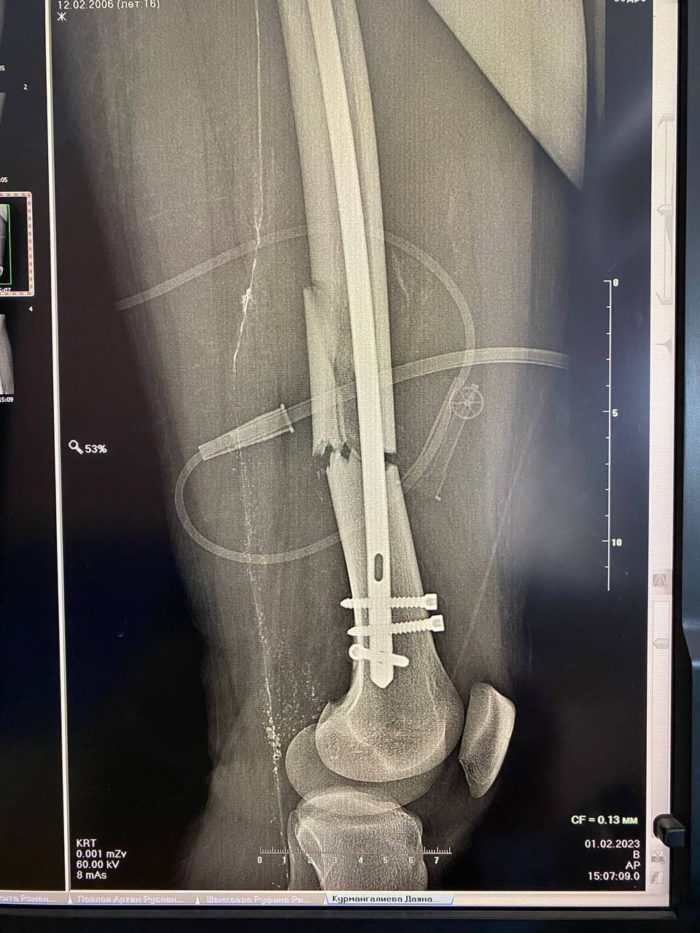

Мальчика доставили в Центр детской хирургии с серьезной сочетанной травмой. У подростка был перелом левой бедренной кости со смещением отломков. Сотрудники ОДКБ пригласили на операцию врачей четвёртой городской больницы, которые имеют серьёзный опыт хирургического лечения подобных травм.

Пациенту провели болокираванный интрамедуллярный стержневой остеосинтез. Спустя два дня ребенок смог вставать на костыли. Боль уменьшилась, отек начал спадать. Через неделю подростка надеются выписать из больницы.

Оперировал юного пациента заведующий кафедрой травматологи и ортопедии ОрГМУ, к. м.н., доцент, врач травматолог-ортопед высшей категории Городской Больницы N4 Андрей Гурьянов. Ассистентами выступили травматологи ОДКБ Иван Четвериков и Александр Бугаев.